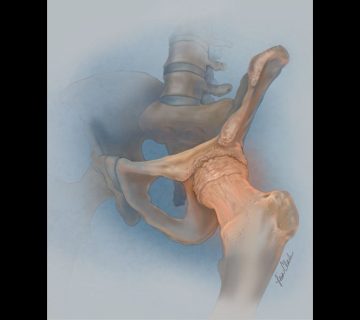

جراحی بدون پروتز مفصل ران (Girdlestone)

روش: در جراحی Girdlestone، سر استخوان ران (توپ مفصل ران) و گاهی بخشی از گردن استخوان ران بهطور جراحی برداشته میشود. در این روش، پروتز یا جایگزین مصنوعی (پروتز) استفاده نمیشود و مفصل بدون سر توپ باقی میماند.

موارد استفاده: این روش جراحی معمولا در مواردی انجام میشود که تعویض مفصل ران با شکست مواجه شده (مثلاً بهدلیل عفونت، فرسایش شدید، یا دررفتگی مکرر) یا در بیمارانی که بهعلت آسیب شدید یا عفونت مفصل، کاندیدای مناسب برای تعویض مفصل ران نیستند. همچنین برای کاهش درد در مواردی که دیگر روشهای جراحی مناسب نیستند، استفاده میشود.

نتیجه: نتیجه این جراحی یک “مفصل ناپایدار” است، که در آن پا از طریق بافت نرم به لگن متصل میشود، بدون یک مفصل عملکردی. این معمولا باعث کوتاه شدن اندام، کاهش دامنه حرکتی و لنگش آشکار میشود. با این حال، این روش میتواند درد را به طور موثری کاهش دهد و منبع عفونت یا ناپایداری را از بین ببرد. بیماران معمولا پس از این جراحی به وسایل کمکی مانند عصا یا واکر نیاز دارند.